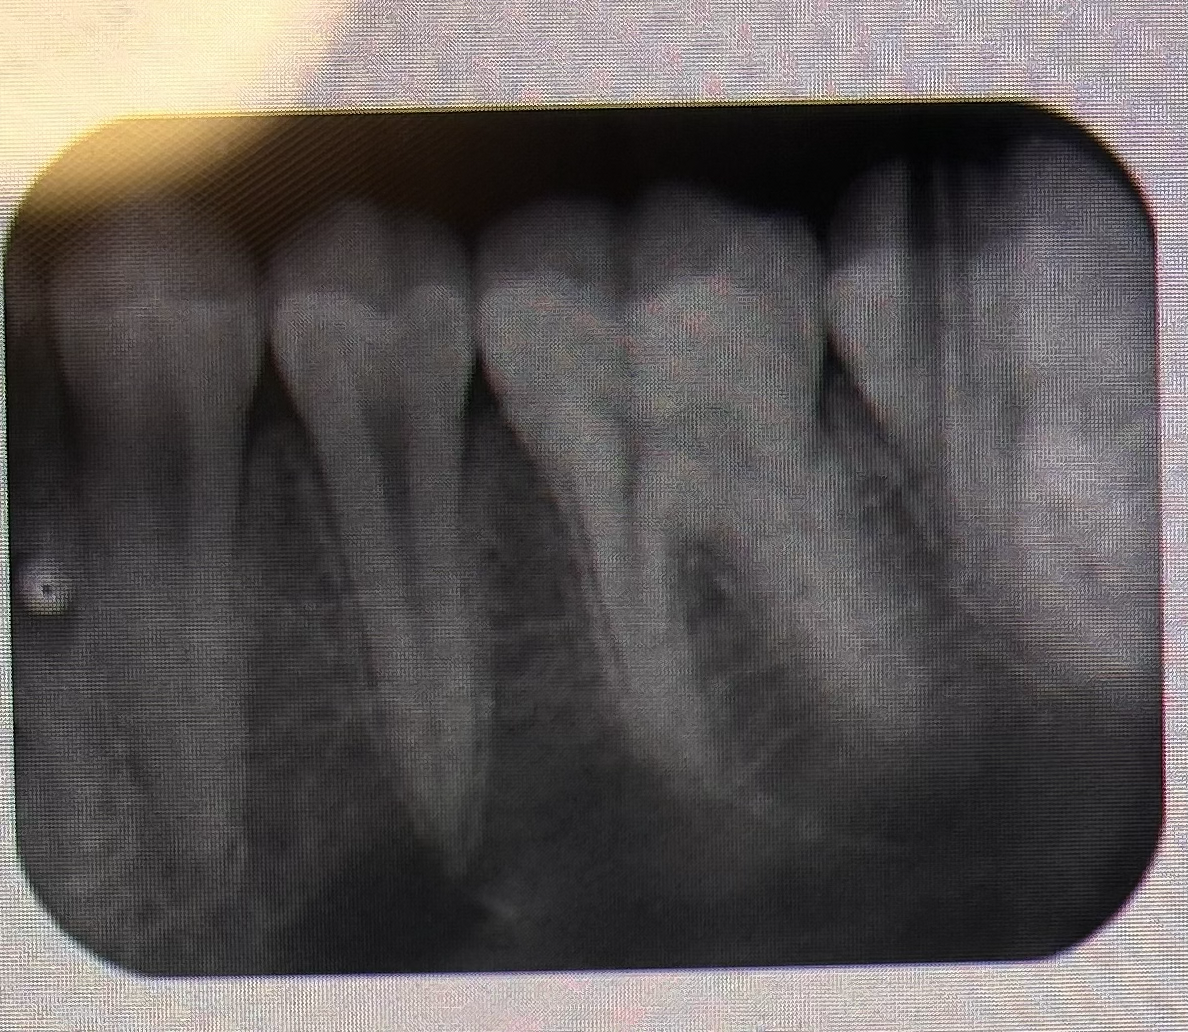

THE PROCESSING ERROR DEPICTED IN THE PICTURE CAN BE DESCRIBED AS WHAT? THE CAUSE WAS DUE TO:

SCRATCHED FILM

DEVELOPER SOFTEN THE EMULSION, LEAVING IT SCRATCHED AND CAREFUL HANDLING, ESPECIALLY BEFORE FIXING, WILL PREVENT SCRATCHES